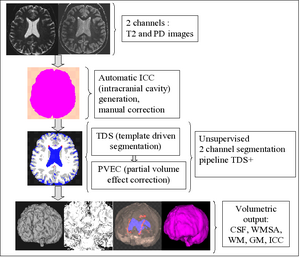

- 9.15 New EMSegment Module in Slicer3